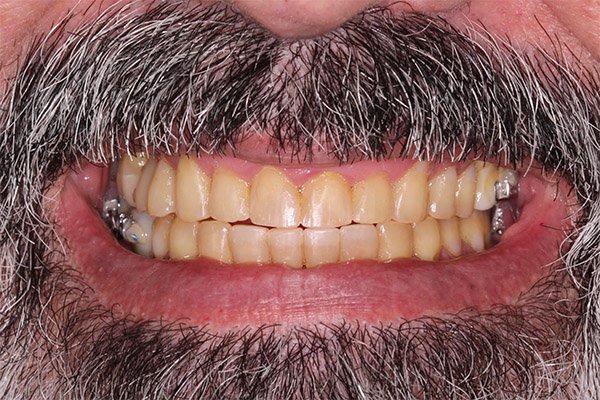

Antes e Depois

IMAGENS REAIS – sem qualquer tipo de manipulação!